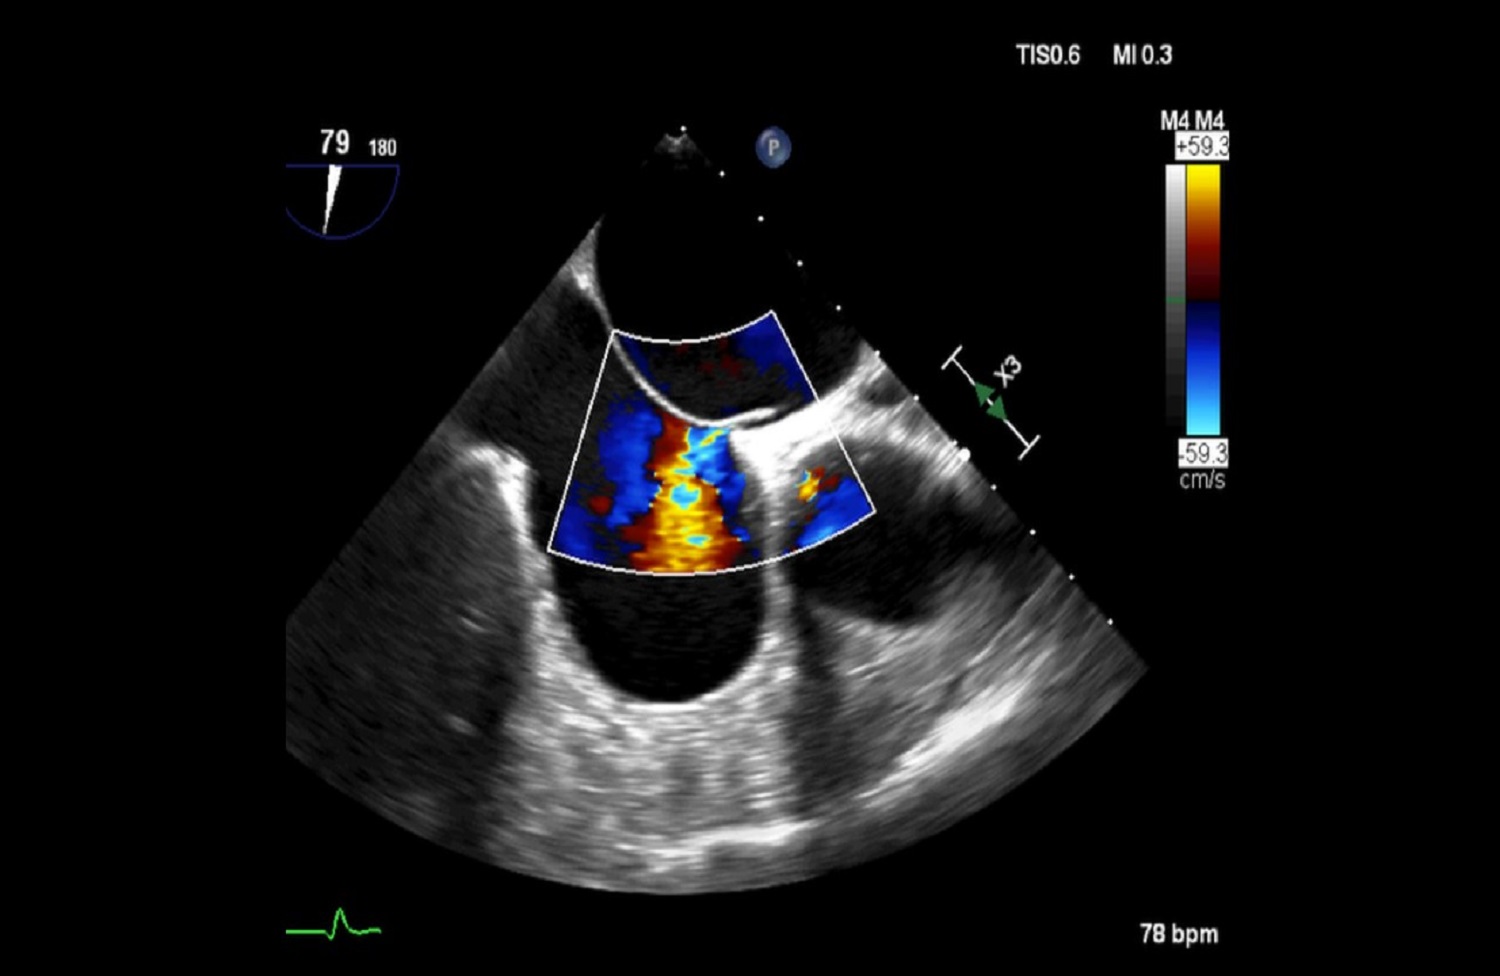

Pracownia Echokardiograficzna Kliniki posiada Akredytację Klasy C (najwyższy poziom referencyjny) przyznaną przez Zarząd Sekcji Echokardiografii Polskiego Towarzystwa Kardiologicznego. W ciągu roku wykonywanych jest tu łącznie ponad 3600 badań echokardiograficznych przezklatkowych, przezprzełykowych i prób z dobutaminą.

W Pracowni badani są pacjenci hospitalizowani w oddziałach Kliniki oraz we wszystkich pozostałych Klinikach Szpitala Klinicznego Dzieciątka Jezus, a także pacjenci ambulatoryjni kierowani z Poradni Kardiologicznej, Nadciśnienia Tętniczego, Przeciwzakrzepowej, Transplantacyjnej i Nefrologicznej Szpitala. Pracownia ukierunkowana jest na diagnostykę zatorowości płucnej, nadciśnienia płucnego, wad zastawkowych, infekcyjnego zapalenia wsierdzia oraz dysfunkcji lewej komory.

Dzięki wykwalifikowanemu personelowi i nowoczesnemu sprzętowi w Klinice wykonywane są również przezskórne zabiegi zamknięcia ubytków przegrody międzyprzedsionkowej typu II oraz drożnego otworu owalnego, pod kontrolą echokardiografii dwu – i trójwymiarowej.

Na podstawie badań z zastosowaniem przezprzełykowej echokardiografii trójwymiarowej w pracowni kwalifikuje się również pacjentów z ciężką niedomykalnością mitralną w mechanizmie wypadania płatka mitralnego do nowatorskich zabiegów małoinwazyjnej przezkoniuszkowej naprawy zastawki bez użycia krążenia pozaustrojowego. Efektem współpracy z Oddziałem Kardiochirurgii Szpitala Medicover była możliwość monitorowania echokardiograficznego przezprzełykowego dwóch pierwszych w Polsce zabiegów naprawy zastawki mitralnej z użyciem robota chirurgicznego da Vinci.

Echokardiografia przezklatkowa przezprzełykowa obciążeniowa z pełnym obrazowaniem dopplerowskim i trójwymiarowym.